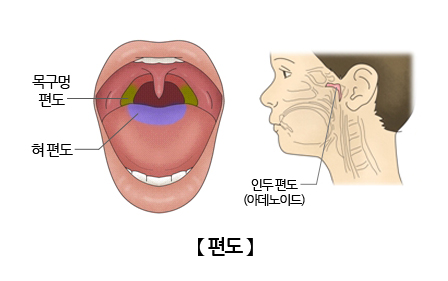

안녕하세요^ 무사하고 건강에 행복한 삶을 영위하고 싶은 생활건강 인플루언서 땡큐입니다.^^ 편도선에 생기는 악취를 가진 좁은 정도의 크기부터 손톱 정도의 크기까지 다양합니다.입 냄새를 유발하는 원인으로 구개편도선 표면에 존재하는 편도선이라는 부위에서 분비된 침소체가 구강 내 이물질과 섞여 생깁니다. 편도결석은 칼슘의 인산염과 탄산염으로 구성되어 있어 침 분비나 혀의 움직임에 의해 삼키거나 기침에 의해 반사적으로 외부로 나오게 됩니다. 편도결석은 보통 나쁜 냄새를 가지고 있어 휘발성 황화합물을 비롯한 악취를 유발하는 원인물질이 되고 식욕까지 변하기도 합니다. 심한 경우 병원에서 편도 구멍을 봉합하는 수술을 받아야 합니다. 그럼 편도결석의 원인과 증상, 편도결석을 빼는 방법에 대해 자세히 살펴보겠습니다.

편도결석의 원인

편도선이 표면의 편도선이나 내부에 세균, 백혈구, 세균의 시체, 지방산, 음식물 잔류물 등이 쌓여 생깁니다. 자연적으로 배설되는 경우가 많은데 배설되는 편도선 표면의 출구나 소와 부분이 좁은 경우 편도선 내부 속에 굳어져 큰 몸이 될 수 있습니다.